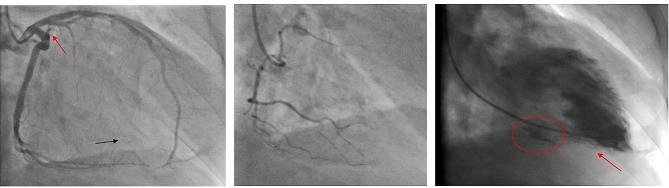

The clinical presentation of left ventricular free wall rupture (LVFWR) varies ranging from uneventful condition to congestive heart failure. Here we report two cases of LVFWR with different clinical presentation and notable outcome. A 53-year-old male presenting emergently with signs of myocardial infarction received immediate coronary angiography and thoracic CT-scan showing occlusion of the first marginal coronary branch without possibility of revascularization and minimal pericardial extravasation. Under ICU surveillance, LVFWR occurred 24 h later and was treated by pericardiocentesis and ECMO support followed by immediate uncomplicated surgical repair. Postoperative therapy-refractory vasoplegia and electromechanical dissociation caused fulminant deterioration and the early death of the patient. The second case is a 76-year old male brought to the emergency room after sudden syncope, clinical sings of pericardial tamponade and suspicion of a type A acute aortic dissection. Immediate CT-angiography excluded aortic dissection and revealed massive pericardial effusion and a hypoperfused myocardial area on the territory of the first marginal branch. Immediate sternotomy under mechanical resuscitation enabled removal of the massive intrapericardial clot and revealed LVFWR. After an uncomplicated surgical repair, an uneventful postoperative course, the patient was discharged with sinus rhythm and good biventricular function. One year after the operation, he is living at home, symptom free.

左心室游离壁破裂(LVFWR)的临床表现多种多样,从无症状到充血性心力衰竭不等。在这里,我们报告了两例具有不同临床表现和显著结局的 LVFWR 病例。一名 53 岁男性因心肌梗死的迹象紧急就诊,立即进行了冠状动脉造影和胸部 CT 扫描,显示第一边缘冠状动脉分支闭塞,无法再通,心包积血量较少。在 ICU 监测下,24 小时后发生 LVFWR,并进行了心包穿刺和 ECMO 支持,随后立即进行了简单的手术修复。术后治疗性血管扩张和电机械分离导致病情迅速恶化,患者早期死亡。第二例是一名 76 岁男性,突发晕厥后被送往急诊室,临床征象为心包填塞,怀疑为急性 A 型主动脉夹层。立即进行 CT 血管造影排除了主动脉夹层,并显示大量心包积液和第一边缘支供血区的低灌注心肌区域。在机械复苏下立即进行胸骨切开术,可清除大量心包积血,并发现 LVFWR。在进行了简单的手术后,患者术后恢复顺利,窦性节律和双心室功能良好。术后一年,他在家中生活,无任何症状。